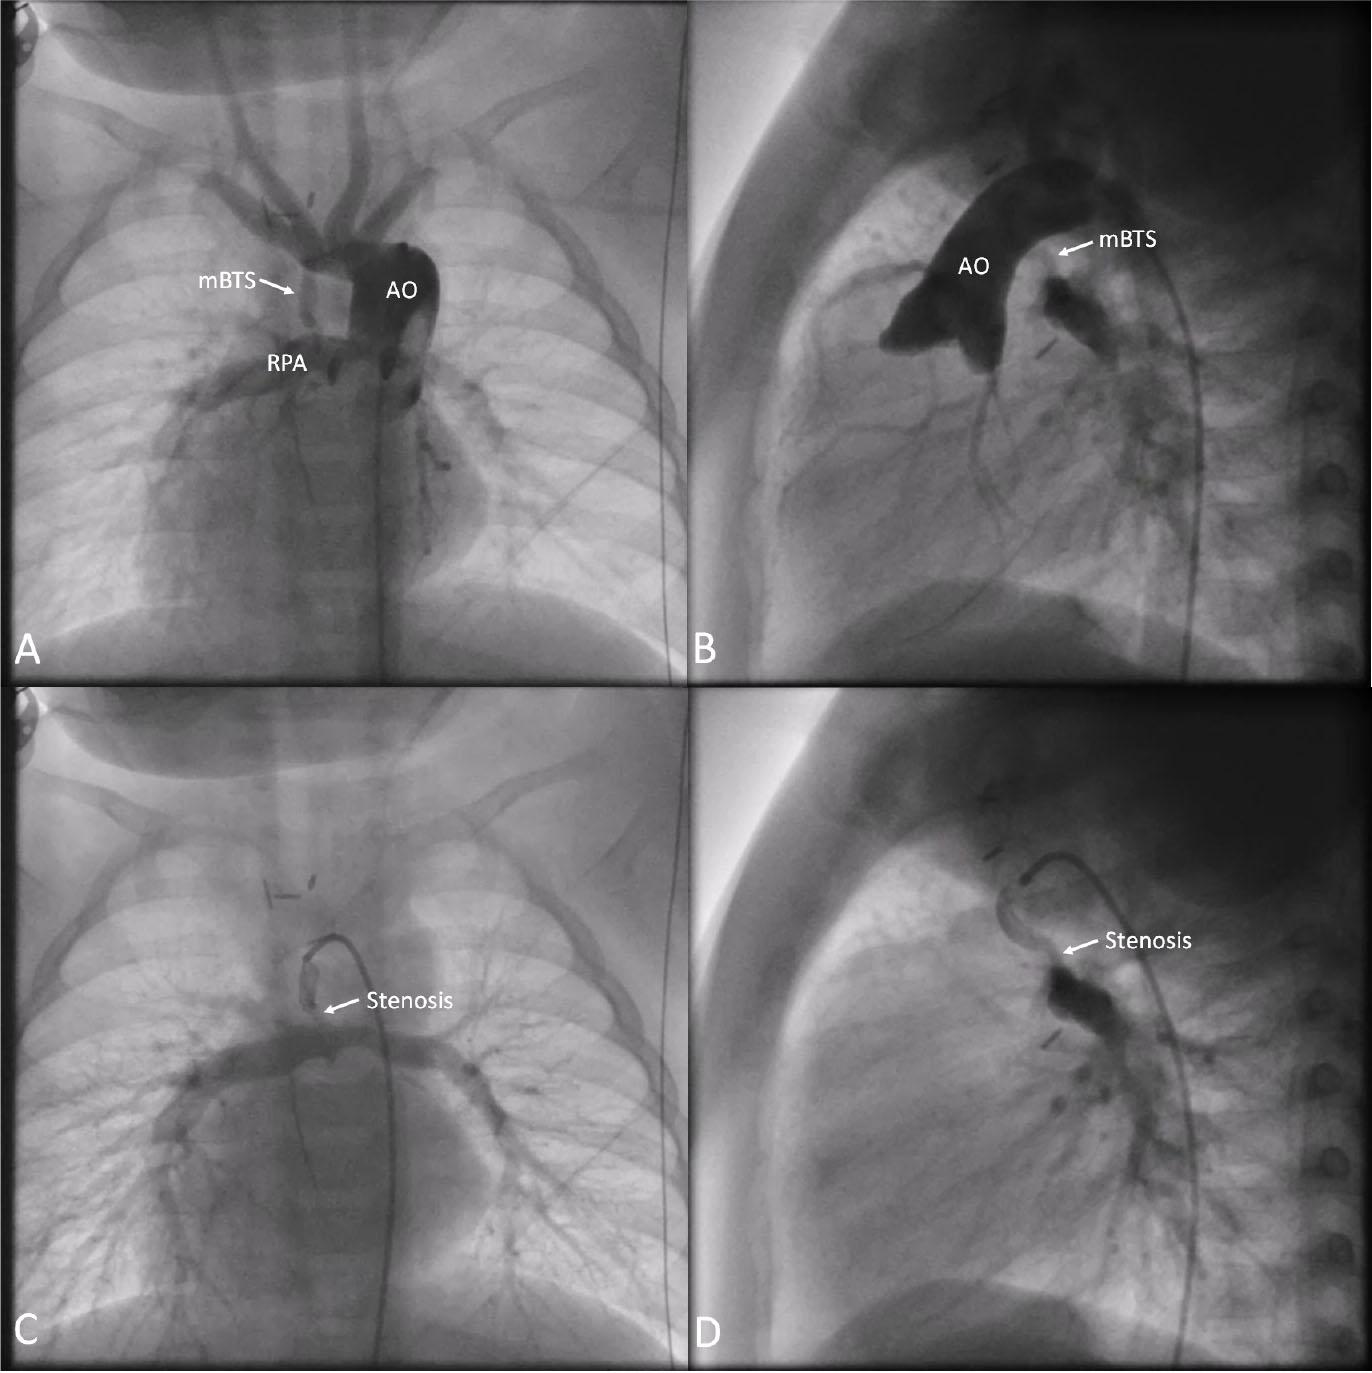

Figure 2